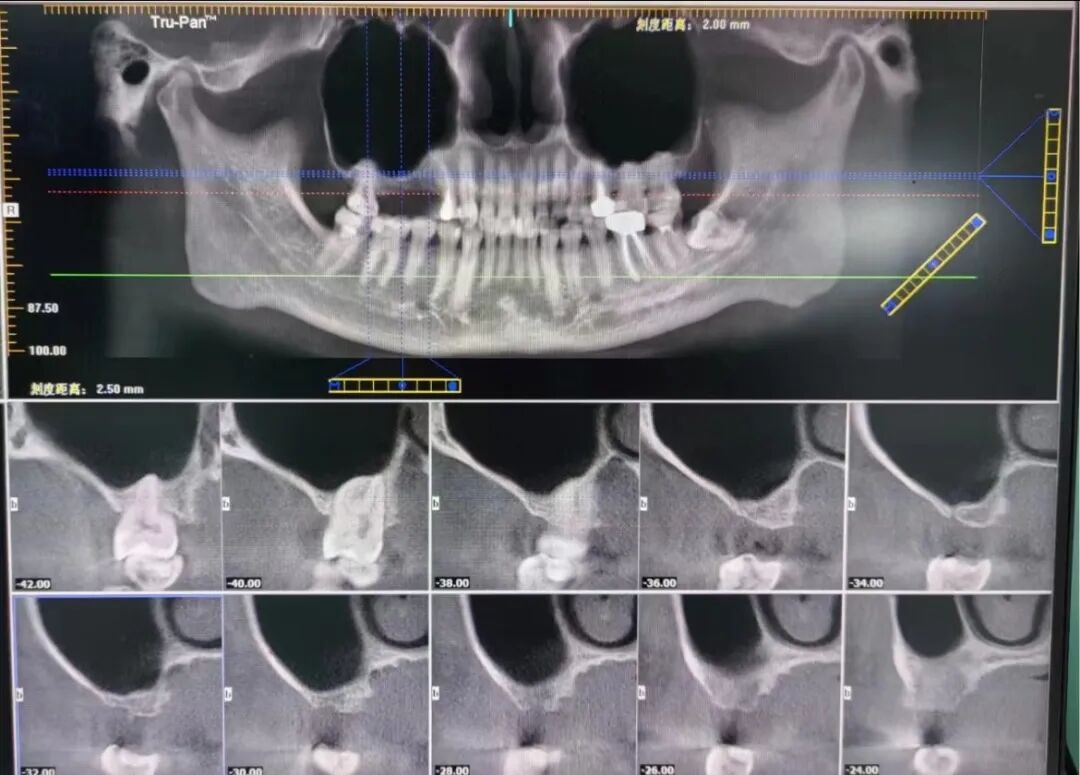

手術(shù)前CT片